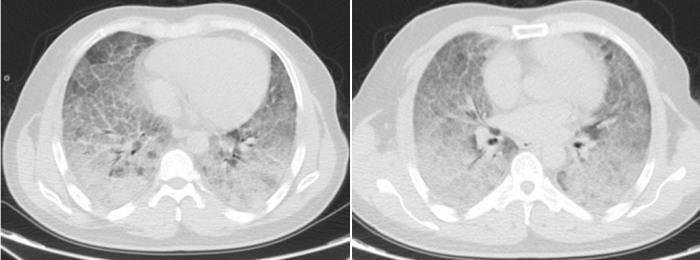

4年前,33岁的李贤因咳嗽、呼吸困难在当地医院进行肺活检确诊为“肺泡蛋白沉积症(PAP)”,这是一种由先天性或继发性因素引起肺表面活性物质清除障碍或产生异常,导致大量脂蛋白沉积在肺泡腔和肺泡巨噬细胞的呼吸系统罕见病,其发病率为每百万人中7—10人。患者可出现进行性呼吸困难、咳嗽、发绀、杵状指等。胸部CT多表现为双肺弥漫性磨玻璃影、“铺路石征”“地图征”。经过“全肺灌洗术”后,李贤病情好转,可以正常生活和工作,未再复查。

李贤胸部CT显示其双肺已呈现“大白肺”状态

历经31天鏖战,李贤的肺部影像从“白茫茫一片”逐渐恢复透亮,鼻导管吸氧下血氧饱和度稳定在90%以上,最终好转出院。患者家属含泪致谢:“是香港马会app 给了他第二次生命!这里的医生护士不仅技术高超,更把我们当家人一样对待!”